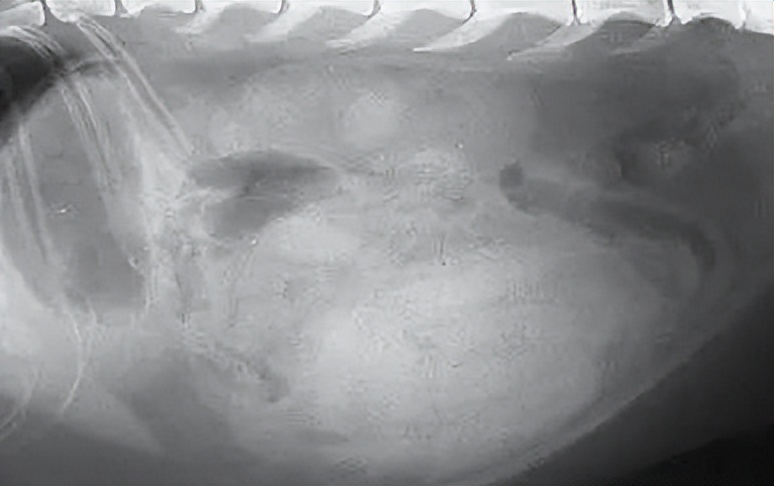

2、图像学检查:x光片或超声波检查,确认腹状况。

4、探测性剖腹术:当图像检查不能确认腹腔内的情况时,需要直接打开腹腔进行检查、取样和测试,以确认肿瘤的情况。